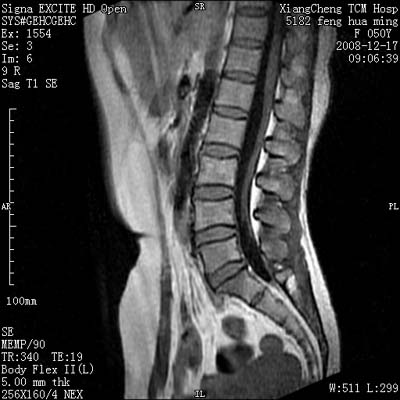

患者,女,50岁,左侧腹股沟及其下方疼痛、酸沉2年。

请各位战友看一下l4-5椎间盘后方椎管内是病灶吗?马尾神经到此处是不是终止了?

腰45椎间盘突出,后部影像可能是硬膜囊粘连引起的

l4/5椎间盘突出。后方硬膜囊受压改变。另外,该病人是否并发子宫肌瘤啊

腰45椎间盘突出,马尾终丝聚集:考虑蛛网膜炎症粘连

l4-5轻突,黄韧带增厚,蛛网膜炎症粘连可能

l4/5椎间盘突出;马尾终丝聚集,考虑蛛网膜炎所致。